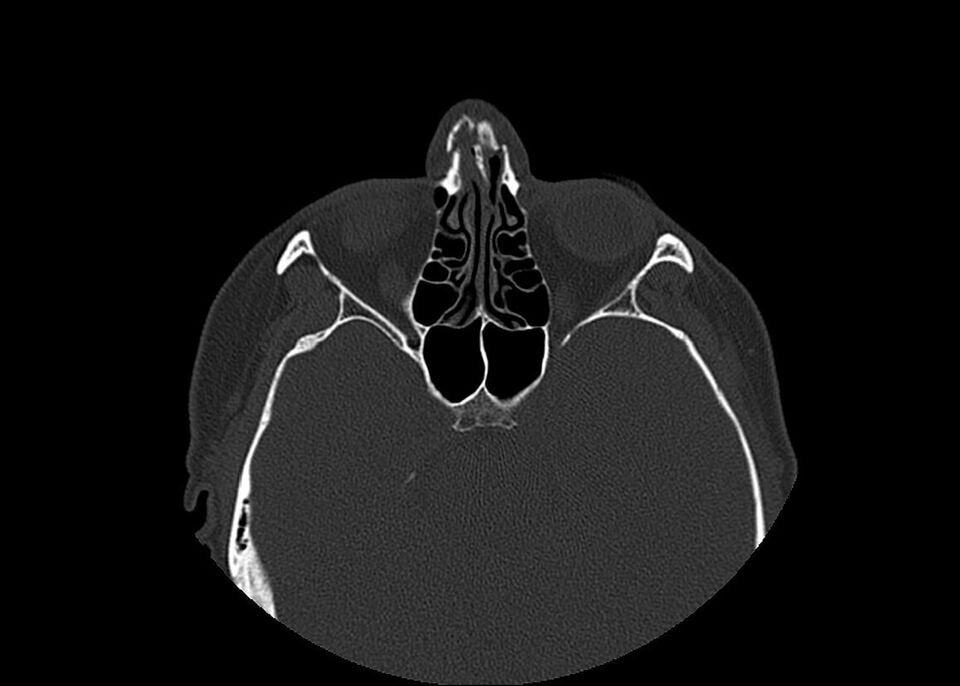

This isn’t the beginning of a novel, but the true story of a woman featured in “Invisibility Is Not A Superpower,” an exhibition that was set up in the atrium of the San Carlo Hospital in Milan, Italy, from Nov. 21 to Dec. 8. Through anonymous photographs and X-rays, the exhibition recounts the tragedy of women arriving at the emergency room and reporting that they have been victims of domestic violence.

“In this exhibition, a voice is given to the bodies and injuries of women who have suffered violence, weaving individual stories into a single narrative,” said photographer Marzia Bianchi. “The lives of the women differ, yet the pattern of violence is repeated, mainly at the hands of a partner, relative or acquaintance.”